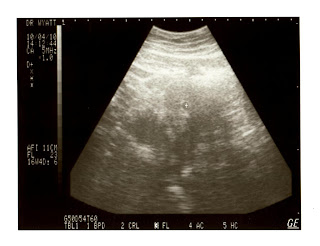

Yes, you’re seeing that correctly! We are expecting our first bundle of joy this coming May 30th. Doctor Wyatt says that everything looks great with the baby and I and that we are making a great team so far. Lets hope it stays that way and the baby treats mommy (WOW, that’s the first time I said/wrote that) nicely.